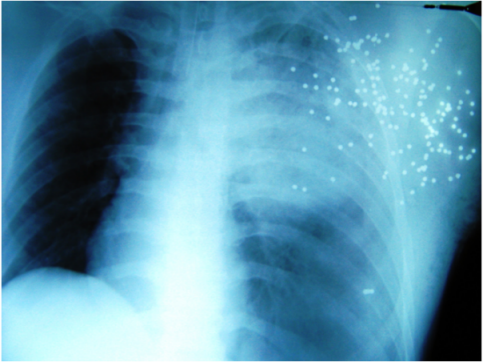

Special complications of shotgun injuries are “projectile embolizations”, which can lead through vessel obstruction to gangrene of lung, cerebral infarction or to vessel arrosion combined with a massive bleeding [5], [6], [7], [8]. To avoid these fatal consequences, a surgical resection is always indicated [5], [8]. Upon arrival at the emergency trauma room the X-ray of the thorax (Figure 4 [Fig. 4]) provides important information. Intraabdominal bleeding increases lethality dramatically [9]. To exclude a pericardial tamponade or intraabdominal bleeding (“free fluid in the abdominal cavity”) a sonography (FAST) of abdomen and thorax should be performed simultaneously [3], [10], [11], [12] [13]. The route of the ricochets determine the operative access [9], [12], [14]. For example in cases of heart or abdominal injuries, median sternotomy and median laparotomy are performed while in cases of a ipsilateral lung injury a lateral thoracotomy is performed [12], [14]. If the patient is haemodynamically stable, whole-body CT scan is the best diagnostic tool for detection of foreign bodies [4]. If there is not enough time for this investigation, because the patient is haemodynamically unstable, the whole-body CT scan has to be performed postoperatively. In cases of emergency thoracotomy [15], the FAST can be performed in the operating room during anesthetic induction. Additionally, the detection of metallic foreign bodies can be performed via C-arm X-ray to determine the operative access on time [6], [14]. After thoracotomy, the immediate bleeding control is decisive. The disconnection of the lung hilum is the fastest control opportunity (because due to the massive bleeding the situs is confusing) and the risk of air embolism is reduced by this maneuver [6], [12], [14], [16]. After suction of blood (most suitable is the cell saver for blood recovery [17]), the selective disconnection of hemorrhage sources follows, e.g. from the lung parenchyma or big vessels. The hilum clamp should be used only for a short time because acute right heart failure could occur. The dimension of resection of the lung has to be limited, because lethality increases proportionally to the loss of parenchyma. A pneumonectomy for example is related to a 80% higher mortality [2], [16], [18], [19], [20]. With a so-called “tractotomy” the shot channels could be opened and supplied with a minimal loss of parenchyma [3], [6], [9], [11], [16], [18]. Essentially, even in cases of no external damage, a pericardiotomy has to be performed to exclude a myocardial lesion [6], [12], [15]. This maneuver is also important if a direct bimanual cardiac massage is necessary [6]. Normally the patients with such massive traumata develop the so-called “deadly triad” [21], [22] with metabolic acidosis, hypothermia, and disseminated intravascular coagulopathy with consequential diffuse bleeding, which is only manageable through intrathoracal tamponade (“packing”) [14], [16], [21], [22], [23]. After these damage control measures the thoracic muscles are only adapted and the pleural cavity is left open [24], [25] to prevent thoracic compartment syndrome [26]. Afterwards, the patient is stabilized in the ICU with correction of the pathophysiological derangement (acidosis, hypothermia and coagulopathy). In a second-look operation (SLO) after 24 to 48 hours [12], [22] the tamponades can be removed and the thorax can be closed definitively. Because of the massive tissue destruction and the inclusions of contaminated metallic and powder fragments, the wounds have to be debrided carefully [2], [27], [28] combined with a high-sensitive antibiotic treatment [3], [27]. An extensive exploration of the wound is also necessary because inclusions of clothes or plastic fragments can not be detected via X-ray. The placement of a vacuum-assisted closure dressing has proven especially valuable [28], [29], [30], leading to quicker wound cleansing and wound granulation compared to traditional wound dressings [28]. That is why remaining defects can be covered more quickly with mesh graft transplantation [27], [28], [29], [30].

Figure 4: X-ray: multiple pellets in the chest